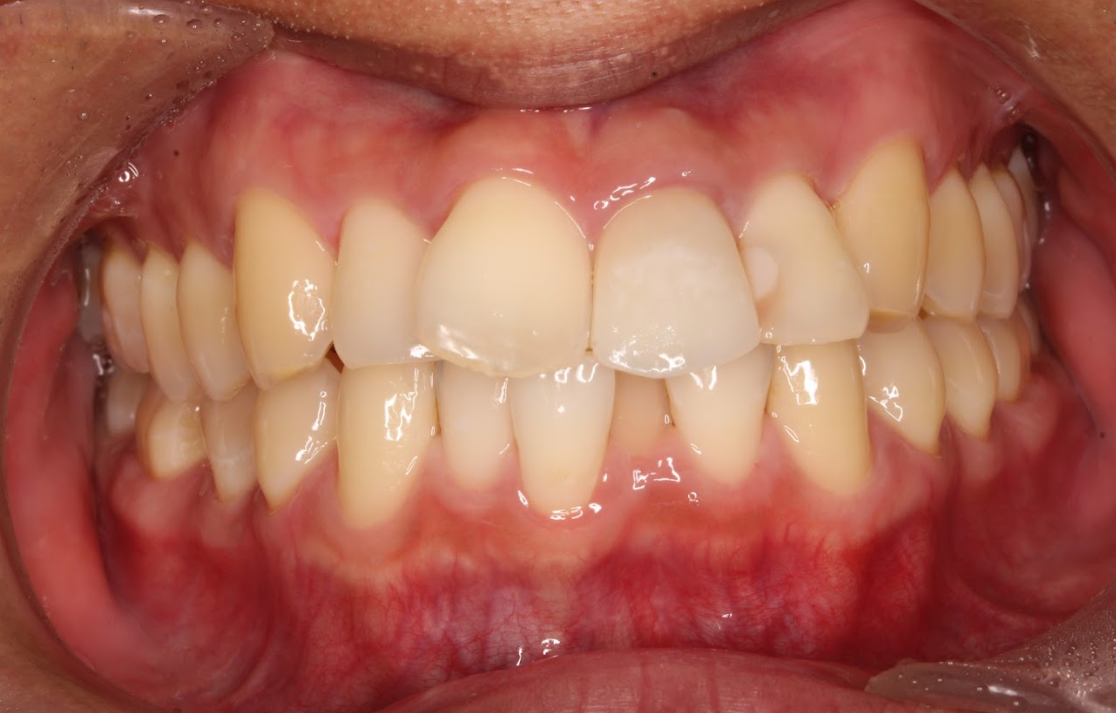

かみ合わせに問題がある

噛み合わせに問題がある場合も、上だけの矯正を行うことはおすすめすることはできません。奥歯の嚙み合わせにズレがある場合、上下の歯の位置関係を同時に調整しないと根本的な改善にはなりません。患者様自身が噛み合わせを気にしていないケースもありますが、上だけの矯正を行うことで嚙み合わせの不正が悪化し、歯の摩耗や顎関節症の原因になることもあります。

重度の不正咬合

歯が大きく重なり合っている重度の叢生や、骨格的に上下の顎の位置に大きなズレがある「上顎前突(出っ歯)」や「下顎前突(受け口)」などの重度の不正咬合では、上だけの矯正では改善できません。重度の不正咬合の場合、奥歯の噛み合わせも整えるために上下の歯列全体を矯正する必要があります。また、場合によっては外科的な処置や抜歯が必要となることもあります。